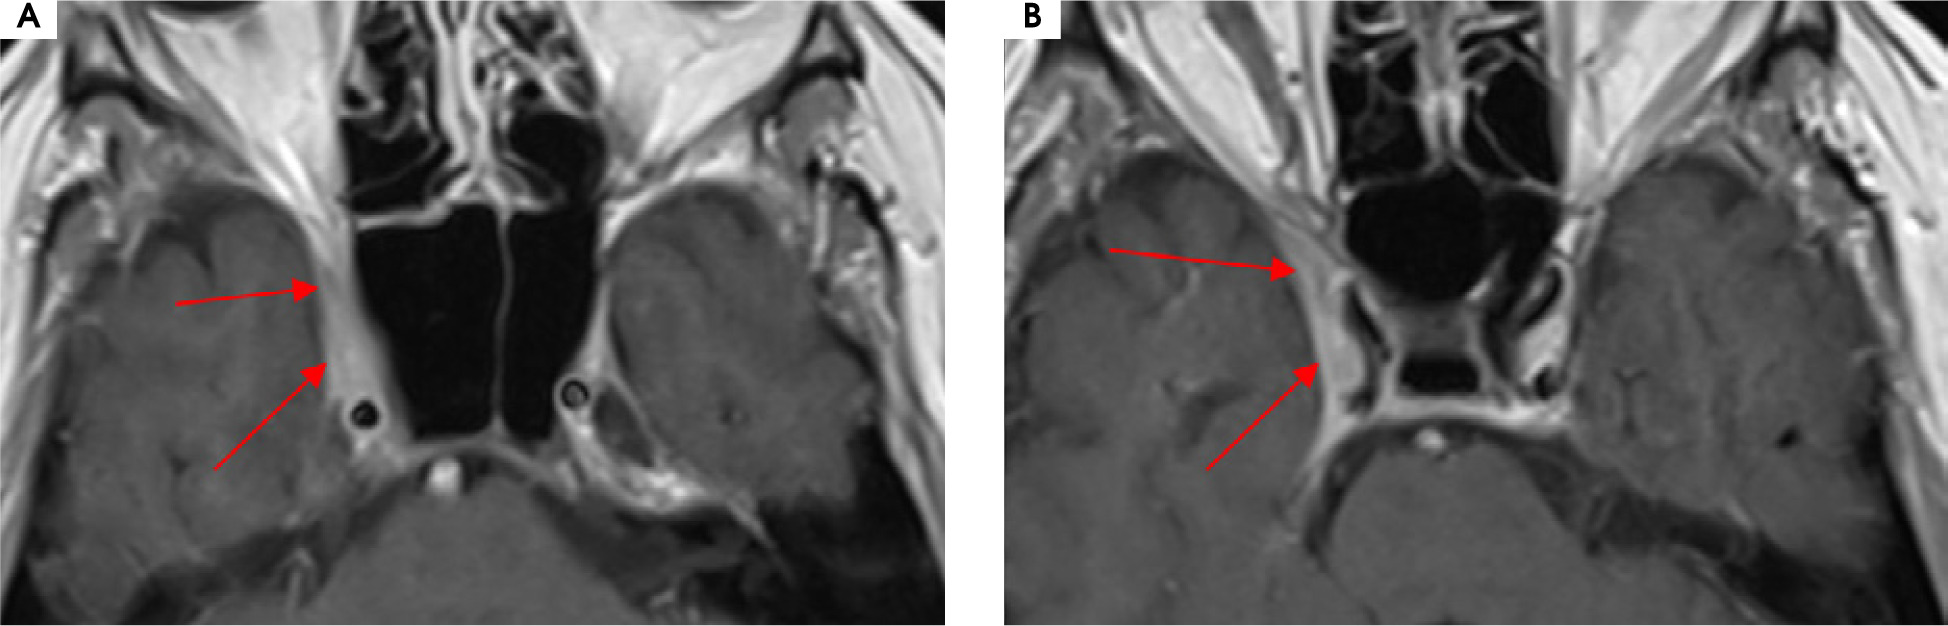

Case 6

A 56-year-old man was admitted to the hospital due to double vision, a problem with the mobility of the right eyeball, and a right-sided headache. The first symptoms were not so obvious due to a prickly headache in the middle of the face, with swelling on its right side. Around 7-8 weeks later typical symptoms appeared, consisting of severe right-sided periorbital headache and ipsilateral eye movement disorder. In the meantime, the patient was treated with antibiotics by a dentist due to suspected peroidontitis. The neurological assessment showed ophthalmoplegia of the right eyeball, ptosis, and exophthalmos. The MRI findings showed asymmetrical reinforcement and thickening up to 6 mm within the cavernous sinus on the right side, laterally directed towards the superior orbital fissure and the top of the orbit. The MRI findings are shown in Figure I and Figure II. Treatment with intravenous steroid was started (1,000 mg of methylprednisolone daily for 7 days), with an improvement of the symptoms, followed by oral steroid of 60 mg of prednisolone in gradually decreasing doses over 36 days. The rapid clinical improvement was observed as shown in Figures III to VI. We also include a video showing the patient’s eye motor functions on the 7th day of the treatment.

Figure II

Patient number 6. Axial MRI T1 sequences with contrast showing asymmetrical reinforcement within the right caver nous sinus